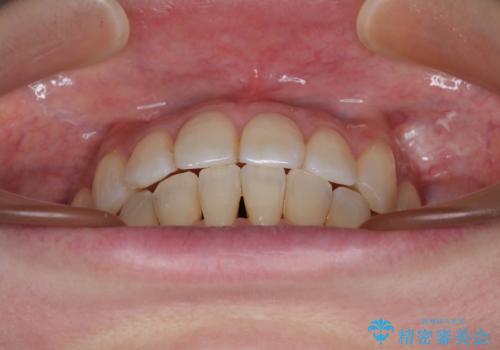

インビザラインによる矯正治療と奥歯のインプラント治療

- 全体的なデコボコと、以前抜歯した歯のスペースを閉じた部分が気になるとのことで来院された患者様です。

左上第一大臼歯を抜歯した際に、スペースを閉じたそうですが、歯が傾斜してものが挟まって不快とのことでした。

インビザライン矯正で全体の歯列と整えるとともに、左上第一大臼歯部にはスペースを作り、インプラントによる補綴治療を行うこととしました。

歯の傾斜が改善され、インプラントによるクラウンが装着されたことで、物が挟まることもなくなりました。